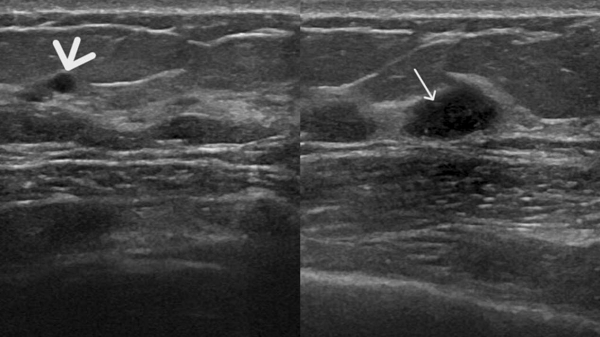

图2 患者A的超声表现图:(粗箭头处)乳腺囊肿,表现为无回声区;(细箭头处)乳腺实性结节,表现为低回声

图4 患者B的超声图像,显示未见钼靶所示钙化灶,但扫查到乳腺实性低回声结节(图中箭头处)